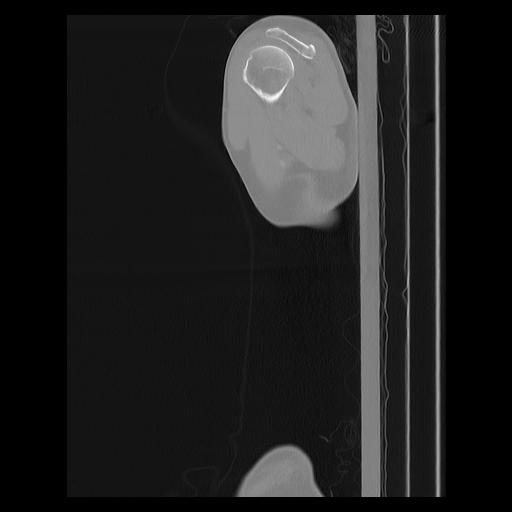

33 PULMON,CE,Sagittal,3.000,PULMON,Sagittal,